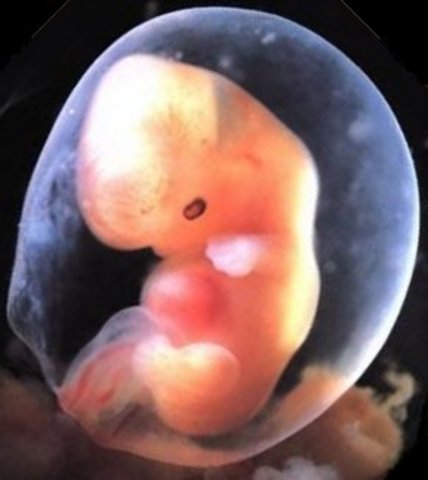

• Week 8

Week 8

Embryo is now 3/4 inch, elbows and toes are becoming visible, starts practicing movements, stomach is being made and face is taking shape.

• Week 9

Week 9

Embryo is 1.2 inches, nose tip, tongue and larynx begin to form. The heart is now complete.